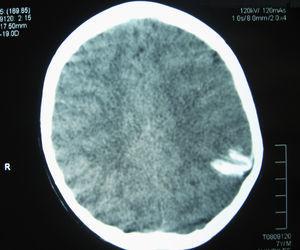

La RM cerebral con gadolinio, realizada un año después del inicio de los episodios, demostró la presencia de un angioma leptomeníngeo en la zona parieto-occipital izquierda, con atrofia cortical subyacente (Figura 2), confirmando la sospecha de SSW sin angioma facial8, 9.

Figura 2. RM con contraste paramagnético (gadolinio) IV: corte coronal, secuencia T1; se aprecia la captación de contraste en la región parieto-occipital izquierda compatible con angioma leptomeníngeo, junto al menor tamaño hemisferio cerebral izquierdo y mayor tamaño ventrículo lateral izquierdo compatibles con hemiatrofia.